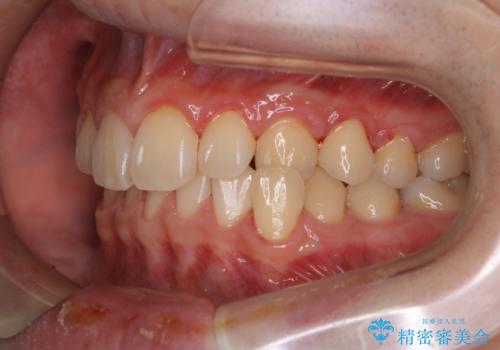

人生で初めてのクリーニングということもあり、プラークや歯石が大量に付いていました。それにより、歯茎の腫れもあり出血も多かったです。これから矯正をスタートしていくため、歯ブラシ指導を行いホームケアを頑張ってもらっています。